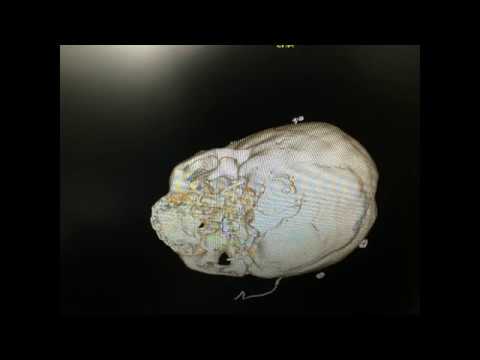

Kafa Kaide ve Beyin Cerrahisi

Prof. Dr. Selçuk Yılmazlar, nöroşirürji alanında klinik ve cerrahi uygulamalarıyla ulusal ve uluslararası düzeyde çalışmalar yürütmekte olup, beyin, omurga ve sinir sistemi hastalıklarının tanı ve tedavisinde modern cerrahi yöntemler uygulamaktadır. Uzmanlık alanları arasında beyin tümörleri, bel ve boyun fıtıkları, damar ve sinir cerrahisi gibi birçok alanda hastalarına hizmet sunmaktadır.